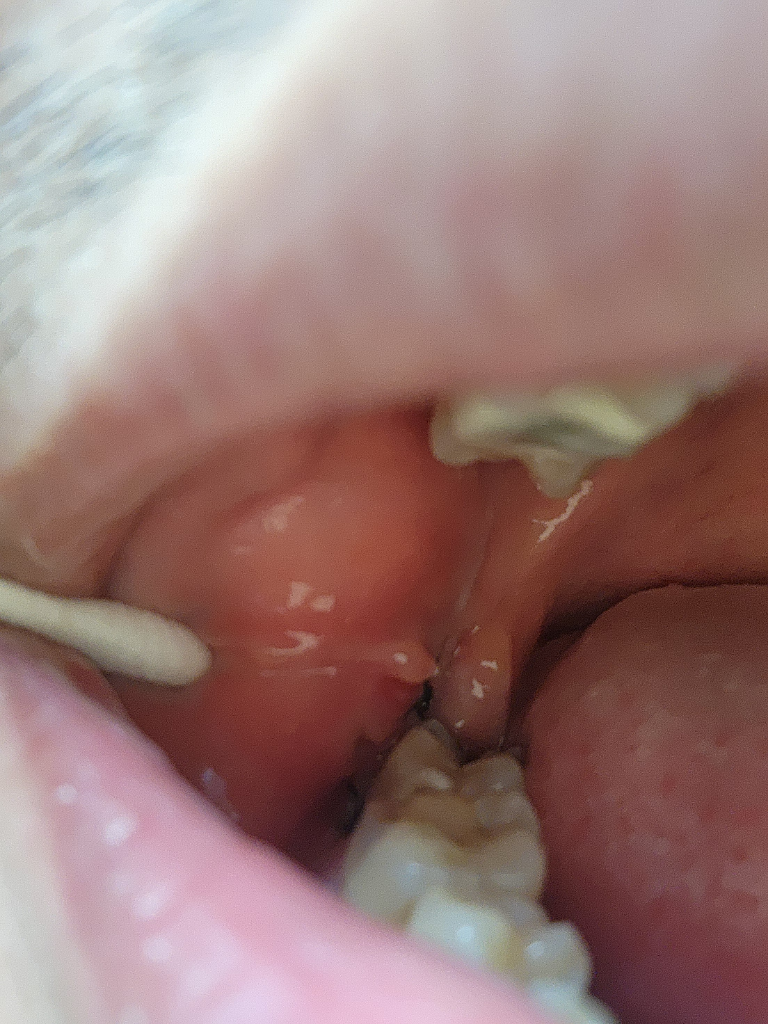

사진을 보면 잘 아물고 있는거 같습니다. 아직 상처가 다 아물지 않아서 그러시는거 같으니 시간이 지나면 괜찮아 지실꺼에요.

사진상 염증의 소견은 보이지 않습니다. 약간의 통증이 생기는 것은 그럴 수 있으며 시간이 지나면 괜찮아질겁니다.

1. 사진상으로는 특별히 큰 이상은 없는 것 같습니다.

2. 발치 후 주의사항만 앞으로도 잘 지켜주시기 바랍니다.

사진으로는 정확하게 확인을 하기 힘들어 보입니다. 발췌한 부위는 최대한 자극을 하지 않는 것이 치유를 앞당길 수 있습니다. 자세한 확인을 위해서 치과에서 진료를 받아보세요

사진상 잘 아물고 있는 것으로 보이며, 발치후에 1-2주간은 통증 및 붓기가 나타날수 있습니다. 통증이 있는 경우 소염진통제 복용을 하는 것이 증상경감에 도움이 됩니다.